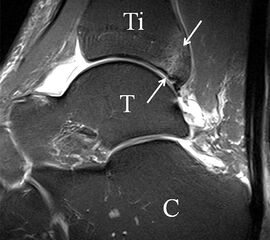

Da also die hintere Syndesmose an der posterioren Tibia inseriert, entspricht eine Fraktur oder Infraktion des hinteren Volkmann`schen Dreiecks funktionell einem knöchernen Ausriss des Ligamentum tibiofibulare posterius (Abb. 18 a und b). Aufgrund der Koinzidenz von Syndesmosenläsionen mit Innenbandverletzungen ist bei der Beurteilung gesondert auf solche zu achten.

b. T2 fs axial. Infraktion des hinteren Volkmann‘schen Dreiecks (schmale, weiße Pfeile). Hier inserierende, intakte, hintere Syndesmose (breite, weiße Pfeile).

Das Ligamentum tibiofibulare posterius (hintere Syndesmose) verläuft flacher und geht nach kranial in das Ligamentum tibiofibulare interosseus und nach kaudal in das Ligamentum intermalleolare posterius über. Letzteres bildet ein artikuläres Labrum zwischen Trochlea und Talus 9.